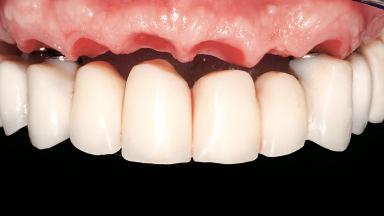

Immediate Loading of Six Implants in the Maxilla and Final Restoration with a Full-Arch CAD/CAM Zirconia FDP

A 63-year-old male patient was referred for a consultation and treatment of partial edentulism in the maxilla. The patient presented with residual anterior teeth and declined a partial removable prosthesis. He reported that the maxillary posterior teeth had been extracted due to mobility and periodontal disease two months before the consultation. The patient’s chief complaint was that his residual maxillary teeth were mobile and that he was unable to chew. The patient’s desire was a stable and comfortable fixed maxillary rehabilitation. The patient was a light smoker (fewer than 10 cigarettes/ day), and his medical history was without significant findings. He was not on any regular medication at the time of consultation. The extraoral examination revealed a normal physiognomy with a correct distribution of the facial thirds. The patient presented a low lip line, and the transition line between teeth and soft tissues was not exposed during a forced smile.

Prosthesis Type FDP

Lip Line No exposure of papillae Exposure of papillae Full exposure of mucosa margin

Occlusal Scheme/Issues Anterior guidance